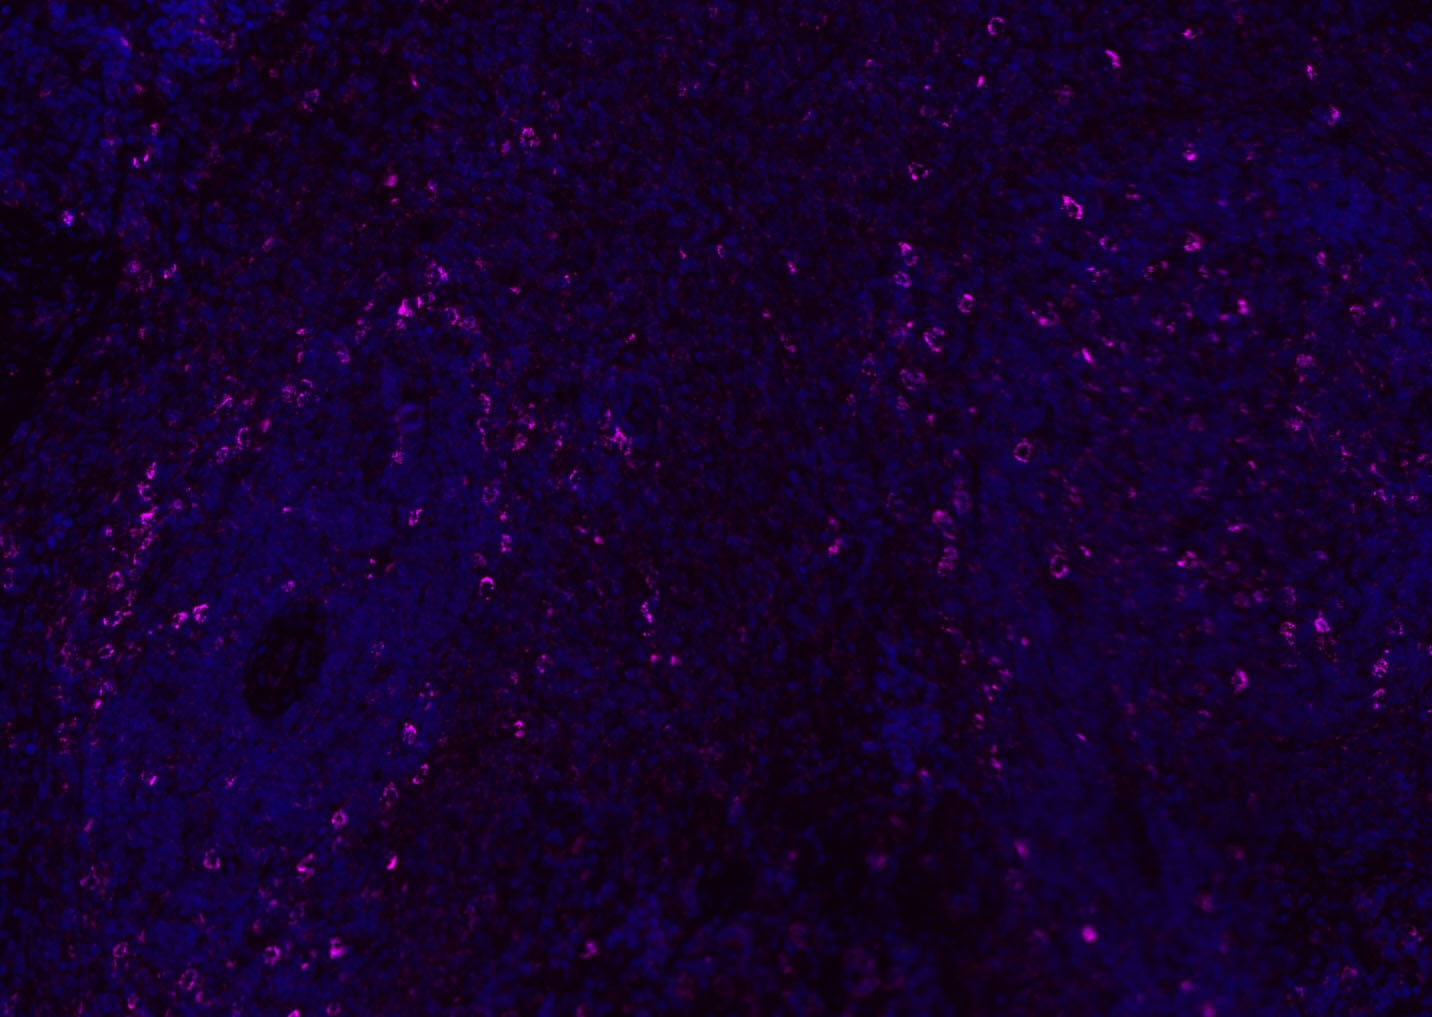

| Verified Activity | 1. Tissue/cell: human lung carcinoma;4% Paraformaldehyde-fixed and paraffin-embedded; Antigen retrieval: citrate buffer (0.01M, pH6.0), Boiling bathing for 15 min; Blocking buffer (normal goat serum) at 37°C for 20 min; Incubation: Anti-CD8 Polyclonal Antibody, Unconjugated (TMAB-00392) 1:200, overnight at 4°C; The secondary antibody was Goat Anti-Rabbit IgG, Cy3 conjugated used at 1:200 dilution for 40 minutes at 37°C. DAPI (5 μg/ml,blue) was used to stain the cell nucleus. 2. Paraformaldehyde-fixed, paraffin embedded (mouse lymphoid); Antigen retrieval by boiling in sodium citrate buffer (pH6.0) for 15 min; Blocking buffer (normal goat serum) at 37°C for 30 min; Antibody incubation with (CD8B) Polyclonal Antibody, Unconjugated (TMAB-00392) at 1:200 overnight at 4°C, followed by a conjugated Goat Anti-Rabbit IgG antibody for 90 minutes, and DAPI for nucleus staining. 3. Paraformaldehyde-fixed, paraffin embedded (rat spleen); Antigen retrieval by boiling in sodium citrate buffer (pH6.0) for 15 min; Blocking buffer (normal goat serum) at 37°C for 30 min; Antibody incubation with (CD8B) Polyclonal Antibody, Unconjugated (TMAB-00392) at 1:200 overnight at 4°C, followed by a conjugated Goat Anti-Rabbit IgG antibody for 90 minutes, and DAPI for nucleus staining. 4. Paraformaldehyde-fixed, paraffin embedded (mouse thymus); Antigen retrieval by boiling in sodium citrate buffer (pH6.0) for 15 min; Blocking buffer (normal goat serum) at 37°C for 30 min; Antibody incubation with (CD8B) Polyclonal Antibody, Unconjugated (TMAB-00392) at 1:200 overnight at 4°C, followed by a conjugated Goat Anti-Rabbit IgG antibody for 90 minutes, and DAPI for nucleus staining. 5. Paraformaldehyde-fixed, paraffin embedded (rat lymphoid); Antigen retrieval by boiling in sodium citrate buffer (pH6.0) for 15 min; Blocking buffer (normal goat serum) at 37°C for 30 min; Antibody incubation with (CD8B) Polyclonal Antibody, Unconjugated (TMAB-00392) at 1:200 overnight at 4°C, followed by a conjugated Goat Anti-Rabbit IgG antibody for 90 minutes, and DAPI for nucleus staining. 6. Paraformaldehyde-fixed, paraffin embedded (rat thymus); Antigen retrieval by boiling in sodium citrate buffer (pH6.0) for 15 min; Blocking buffer (normal goat serum) at 37°C for 30 min; Antibody incubation with (CD8B) Polyclonal Antibody, Unconjugated (TMAB-00392) at 1:200 overnight at 4°C, followed by a conjugated Goat Anti-Rabbit IgG antibody for 90 minutes, and DAPI for nucleus staining. 7. Paraformaldehyde-fixed, paraffin embedded (human tonsil); Antigen retrieval by boiling in sodium citrate buffer (pH6.0) for 15 min; Blocking buffer (normal goat serum) at 37°C for 30 min; Antibody incubation with (CD8B) Polyclonal Antibody, Unconjugated (TMAB-00392) at 1:200 overnight at 4°C, followed by a conjugated Goat Anti-Rabbit IgG antibody for 90 minutes, and DAPI for nucleus staining. 8. Paraformaldehyde-fixed, paraffin embedded (mouse lymphoid); Antigen retrieval by boiling in sodium citrate buffer (pH6.0) for 15 min; Blocking buffer (normal goat serum) at 37°C for 30 min; Antibody incubation with (CD8B) Polyclonal Antibody, Unconjugated (TMAB-00392) at 1:200 overnight at 4°C, followed by a conjugated Goat Anti-Rabbit IgG antibody for 90 minutes, and DAPI for nucleus staining. 9. Paraformaldehyde-fixed, paraffin embedded (rat thymus); Antigen retrieval by boiling in sodium citrate buffer (pH6.0) for 15 min; Blocking buffer (normal goat serum) at 37°C for 30 min; Antibody incubation with (CD8B) Polyclonal Antibody, Unconjugated (TMAB-00392) at 1:200 overnight at 4°C, followed by a conjugated Goat Anti-Rabbit IgG antibody for 90 minutes, and DAPI for nucleus staining. 10. Paraformaldehyde-fixed, paraffin embedded (human tonsil); Antigen retrieval by boiling in sodium citrate buffer (pH6.0) for 15 min; Blocking buffer (normal goat serum) at 37°C for 30 min; Antibody incubation with (CD8B) Polyclonal Antibody, Unconjugated (TMAB-00392) at 1:200 overnight at 4°C, followed by a conjugated Goat Anti-Rabbit IgG antibody for 90 minutes, and DAPI for nucleus staining. 11. Paraformaldehyde-fixed, paraffin embedded (mouse spleen); Antigen retrieval by boiling in sodium citrate buffer (pH6.0) for 15 min; Blocking buffer (normal goat serum) at 37°C for 30 min; Antibody incubation with (CD8B) Polyclonal Antibody, Unconjugated (TMAB-00392) at 1:200 overnight at 4°C, followed by a conjugated Goat Anti-Rabbit IgG antibody for 90 minutes, and DAPI for nucleus staining. 12. Paraformaldehyde-fixed, paraffin embedded (rat lymphoid); Antigen retrieval by boiling in sodium citrate buffer (pH6.0) for 15 min; Blocking buffer (normal goat serum) at 37°C for 30 min; Antibody incubation with (CD8B) Polyclonal Antibody, Unconjugated (TMAB-00392) at 1:200 overnight at 4°C, followed by a conjugated Goat Anti-Rabbit IgG antibody for 90 minutes, and DAPI for nucleus staining. 13. Paraformaldehyde-fixed, paraffin embedded (Rat lymphoid); Antigen retrieval by boiling in sodium citrate buffer (pH6.0) for 15 min; Blocking buffer (normal goat serum) at 37°C for 30 min; Antibody incubation with (CD8B) Polyclonal Antibody, Unconjugated (TMAB-00392) at 1:100 overnight at 4°C, followed by a conjugated Goat Anti-Rabbit IgG antibody for 90 minutes, and DAPI for nucleus staining. 14. Paraformaldehyde-fixed, paraffin embedded (mouse thymus); Antigen retrieval by boiling in sodium citrate buffer (pH6.0) for 15 min; Blocking buffer (normal goat serum) at 37°C for 30 min; Antibody incubation with (CD8B) Polyclonal Antibody, Unconjugated (TMAB-00392) at 1:100 overnight at 4°C, followed by a conjugated Goat Anti-Rabbit IgG antibody for 90 minutes, and DAPI for nucleus staining. 15. Paraformaldehyde-fixed, paraffin embedded (mouse spleen); Antigen retrieval by boiling in sodium citrate buffer (pH6.0) for 15 min; Blocking buffer (normal goat serum) at 37°C for 30 min; Antibody incubation with (CD8B) Polyclonal Antibody, Unconjugated (TMAB-00392) at 1:100 overnight at 4°C, followed by a conjugated Goat Anti-Rabbit IgG antibody for 90 minutes, and DAPI for nucleus staining. 16. Paraformaldehyde-fixed, paraffin embedded (rat spleen); Antigen retrieval by boiling in sodium citrate buffer (pH6.0) for 15 min; Blocking buffer (normal goat serum) at 37°C for 30 min; Antibody incubation with (CD8B) Polyclonal Antibody, Unconjugated (TMAB-00392) at 1:100 overnight at 4°C, followed by a conjugated Goat Anti-Rabbit IgG antibody for 90 minutes, and DAPI for nucleus staining. 17. Paraformaldehyde-fixed, paraffin embedded (rat thymus); Antigen retrieval by boiling in sodium citrate buffer (pH6.0) for 15 min; Blocking buffer (normal goat serum) at 37°C for 30 min; Antibody incubation with (CD8B) Polyclonal Antibody, Unconjugated (TMAB-00392) at 1:100 overnight at 4°C, followed by a conjugated Goat Anti-Rabbit IgG antibody for 90 minutes, and DAPI for nucleus staining. 18. Paraformaldehyde-fixed, paraffin embedded (human tonsil); Antigen retrieval by boiling in sodium citrate buffer (pH6.0) for 15 min; Blocking buffer (normal goat serum) at 37°C for 30 min; Antibody incubation with (CD8B) Polyclonal Antibody, Unconjugated (TMAB-00392) at 1:100 overnight at 4°C, followed by a conjugated Goat Anti-Rabbit IgG antibody for 90 minutes, and DAPI for nucleus staining. 19. Paraformaldehyde-fixed, paraffin embedded (mouse lymphoid); Antigen retrieval by boiling in sodium citrate buffer (pH6.0) for 15 min; Blocking buffer (normal goat serum) at 37°C for 30 min; Antibody incubation with (CD8B) Polyclonal Antibody, Unconjugated (TMAB-00392) at 1:100 overnight at 4°C, followed by a conjugated Goat Anti-Rabbit IgG antibody for 90 minutes, and DAPI for nucleus staining. ![]() ![]() ![]() ![]() ![]() ![]() ![]() ![]() ![]() ![]() ![]() ![]() ![]() ![]() ![]() ![]() ![]() ![]() ![]() |